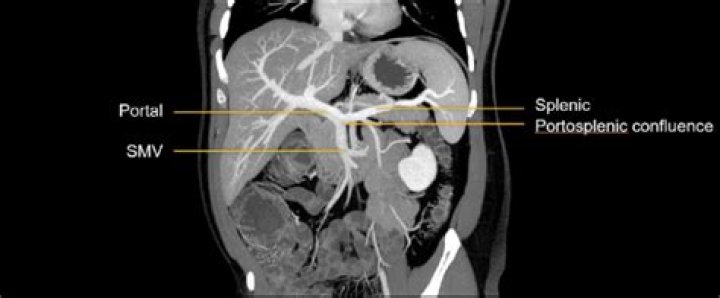

What is the portal splenic confluence?

Lienal vein is an old term for splenic vein. The portal vein is usually formed by the confluence of the superior mesenteric and splenic veins and also receives blood from the inferior mesenteric, left and right gastric veins, and cystic veins. Conditions involving the portal vein cause considerable illness and death.

what is the main portal vein? The portal vein (PV) (sometimes referred to as the main or hepatic portal vein) is the main vessel in the portal venous system and drains blood from the gastrointestinal tract and spleen to the liver.